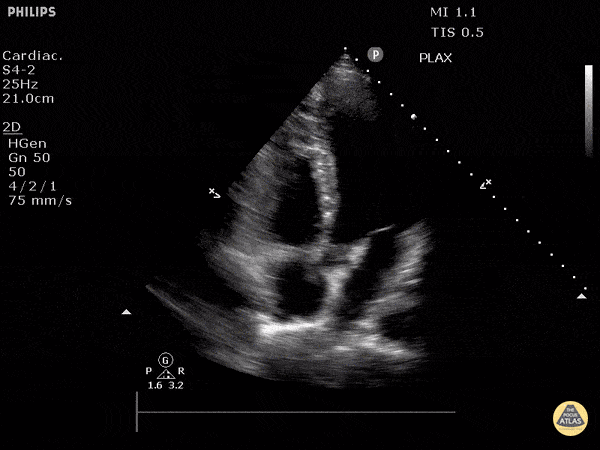

Normal Cardiac Anatomy - Apical 5 Chamber View